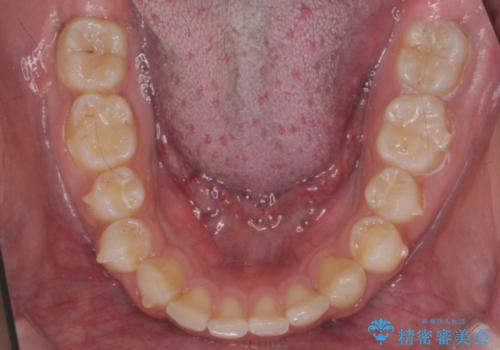

出っ歯が気になる 歯をぬかずに治療

- 前歯が出ているのを気にして来院。

左のかみ合わせが1本分ずれていましたが、機能的には問題ないのでそのまま変えずに治療しています。

ずれている分を、上の歯を1本抜くか(ワイヤー矯正になります)、右上の奥歯を1本分後ろに送るか、そのまま前歯を並べるのかを選んでいただきました。

右のかみ合わせをそのままに、最小限の動かし方で見た目を改善しました。